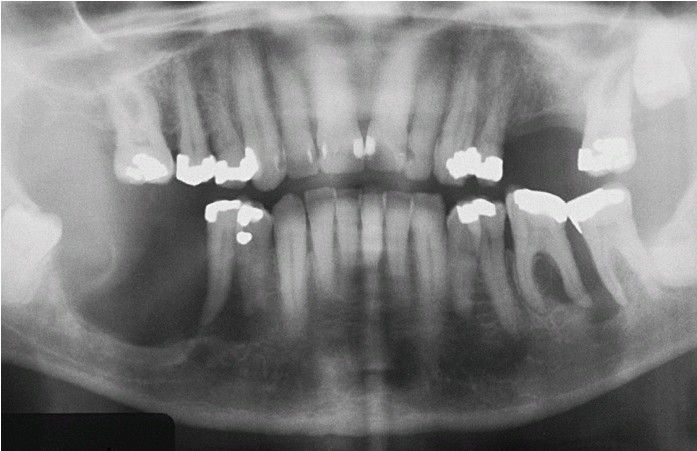

Langerhans Cell Histiocytosis

Severe bone loss in the mandibular molar regions that resembles advanced periodontitis.

Periodontitis